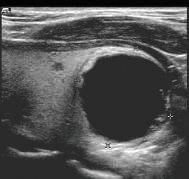

Refraction causes bending of the sound beam so that targets not along the axis of the transducer are insonated. Their reflections are then detected and displayed in the image. This may cause structures to appear in the image that actually lie outside the volume the investigator assumes is being examined (see Fig 1.7). Similarly, side lobes may produce confusing echoes that arise from sound beams that lie outside the main ultrasound beam (Fig. 1.28). These side lobe artifacts are of clinical importance because they may create the impression of structures or debris in fluid-filled structures (Fig. 1.29). Side lobes may also result in errors of measurement by reducing lateral resolution. As with most other artifacts, repositioning the transducer and its focal zone or using a different transducer will usually allow the differentiation of artifactual from true echoes.

FIG. 1.29 Side Lobe Artifact. Transverse image of the gallbladder reveals a bright internal echo (A) that suggests a band or septum within the gallbladder. This is a side lobe artifact related to the presence of a strong out-of-plane reflector (B) medial to the gallbladder. The low-level echoes in the dependent portion of the gallbladder (C) are also artifactual and are caused by the same phenomenon. Side lobe and slice thickness artifacts are of clinical importance because they may create the impression of debris in fluid-filled structures.

in what is actually a simple ovarian cyst.